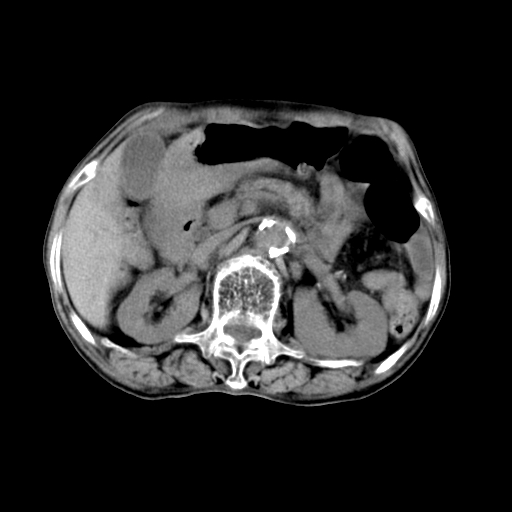

女,68岁,腹胀、恶心两周,先做ct平扫,当时家属不同意强化,6天后家属要求增强扫描。

1、胃窦癌; 2、局灶性脂肪肝。

1、胃窦癌?建议行胃镜!; 2、局灶性脂肪肝。

1)不排除胃窦癌;建议行胃镜检查。 2)局灶性脂肪肝。腹水。

考虑:胃窦ca,腹水,脂肪肝

1)胃窦壁厚,考虑胃窦癌?建议行胃镜检查。 2)局灶性脂肪肝。